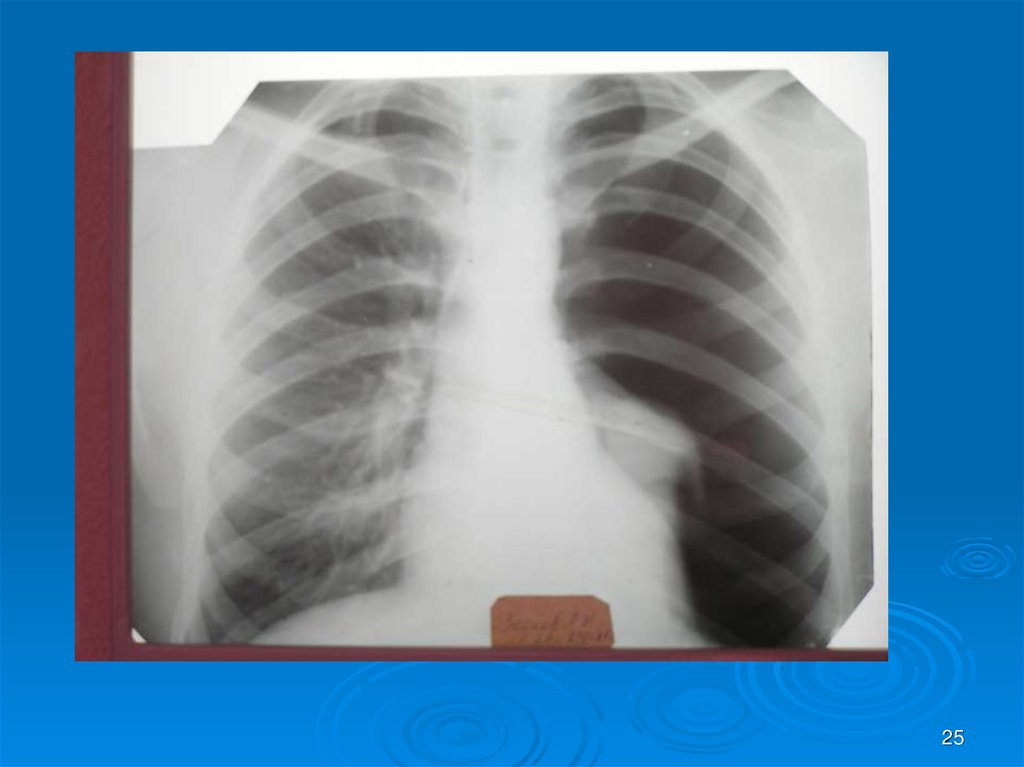

25.

25